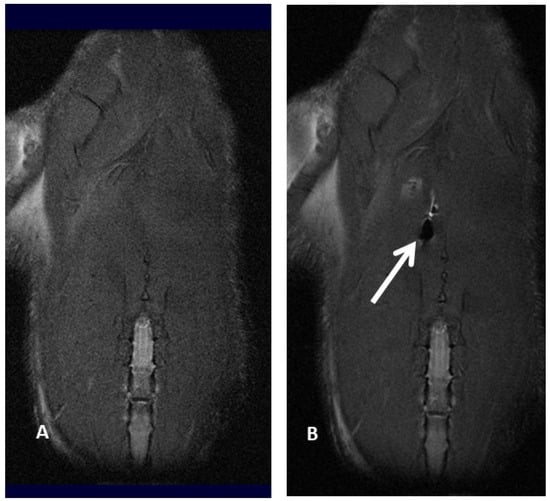

3. Imaging

Molecular imaging provides a better knowledge of cell fate after transplantation, thus optimizing cell therapy results. In fact, it has already been reported that after systemic injection, MSC amass in the lung and vascular beds of other organs and tissues, thus reducing the number of MSC moving to the target site for therapy [26,27]. Positron emission tomography (PET), magnetic resonance imaging (MRI), single-photon emission computed tomography (SPECT), bioluminescence imaging (BLI) and fluorescence imaging (FLI) are several imaging techniques able to visualize signals produced by labeled MSC, thus making it possible to properly track MSC, revealing cell fate, migration and implant after transplantation. Molecular imaging plays a pivotal role in determining the appropriate cell type, transfer technique, cell dosage, and treatment window, as well as in evaluating potential toxic side effects by identifying early cell graft modification into neoplasms, which cannot be detected in a timely manner by standard imaging technique. In addition, molecular imaging of MSC provides useful information about cell survival, proliferation and differentiation within the target area: these data make it possible to optimize the therapeutic dose–response curve, identifying the best dosage and dosing frequency of cell therapy [28,29,30,31,32,33]. To date, imaging and tracking of transplanted MSC have not yet been definitely assessed, and several issues related to MSC migration and engraftment to extra-target sites need to be further assessed before molecular imaging techniques can be safely applied to daily clinical practice. For example, Scharf et coll. have demonstrated that when performing ultrasound-guided MSC intralesional injection for tendonitis, only a few cells remain within collagenous tendon while, on the contrary, many cells scatter to the surrounding fascia, disclosing an MSC greater delocalization than expected [34]. Similarly, extracellular vesicles (EV)—which are paracrine mediators released by MSC under specific conditions, disclosing potential application in cell-based therapies—tend to preferentially migrate to the lung, spleen and liver after systemic administration [35,36,37,38,39,40]. Cellular imaging techniques are not invasive and provide high-resolution images, thus resulting in very important to defining the cell fate after implantation; in experienced hands, they are relatively easy to use, although not widely available (e.g., 8-Tesla MRI for small animals) because of their exclusive use for scientific non-clinical purposes (Figure 2A,B).

Magnetic resonance imaging offers high-resolution images that range from 50 μm in experimental animal models to 300 μm in clinical settings; since it does not rely on ionizing radiations, it is one of the less invasive methods of tracking MSC “in vivo”. However, MSC have to be pre-labeled by some contrast media: among them, there are some positive contrast media, like gadolinium, and some negative contrast media, such as superparamagnetic iron-oxide (SPIO) and ultrasmall superparamagnetic iron-oxide (USPIO), which make it possible to identify and track transplanted MSC within the target environment. Another more recent approach for MSC detection by MRI is MSC labeling by perfluorocarbon (PFC) nanoemulsions, requiring dedicated 19Fluorine MRI. In our personal experience, we compared magnetic resonance imaging of iron-labeled cells and magnetic resonance spectroscopy of fluorine-labeled cells. We explored whether rat bone marrow MSC can be effectively labeled with superparamagnetic iron-oxide (SPIO) nanoparticles and perfluorocarbon (PFC) nanoemulsion formulations without interfering with cell viability and matched magnetic resonance imaging (MRI) and magnetic resonance spectroscopy (MRS) findings from iron-labeled and fluorine-labeled MSC. The SPIO negative contrast enhancement provides an excellent view even in the case of very small numbers of labeled cells but can be easily confused with other sources of magnetic sensitivity effects, like blood vessels or air bleeds, in relation to the anatomical site under evaluation. As prospective clinical applications might include lung tissue evaluation for MSC injection in the repair process and assessing MSC migration and engraftment into the lungs, we also labeled cells with PFC nanoemulsions, which can be identified by 19F MRI. Our finding suggested that both types of contrast agents (PFC and SPIO) can be successfully used for MSC labeling, although further studies were needed to upgrade the efficacy of PFC labeling [47]. In particular, we referred to our previous experience of bronchopleurla fistula (BPF) repair after bronchial disruption following major anatomical lung resection for cancer.

Subsequently, in fact, we investigated the role of 7-Tesla magnetic resonance imaging to track MSC labeled by perfluorocarbon (PFMSC): PFC-based emulsion provided better views in an “in-vivo” rat model compared with USPIO contrast medium, particularly when assessing lung tissue. MSC diffusion to other solid organs, in this case only to the liver, was also better disclosed by PFC-labeled MSC, probably due to the iron content within the liver. A linear decline of delivered PFC-labeled MSC was reported 24 and 48 h after the injection in lung tissue; in nearly half of the observations, PFC-labeled MSC seeding to the liver was reported, with a similar decline over time as observed in the lung. We might argue that MSC locally injected into the lung might scatter to the liver through the blood flow of the cardiac cycle. Nevertheless, considering that about 40% of the rats did not disclose any signal in the liver at time zero, it might be argued that cell migration to the liver only happened when MSC were injected more centrally and thus closer to pulmonary vessels, whereas MSC injected more peripherally in the lung parenchyma were not able to reach the systemic blood flow [50,51].

Figure 2. Magnetic resonance imaging of a rat before (A) and after (B) injection of ferumoxides labeled mesenchymal stromal cell, resulting in an apparent loss of signal (white arrow and black hole).